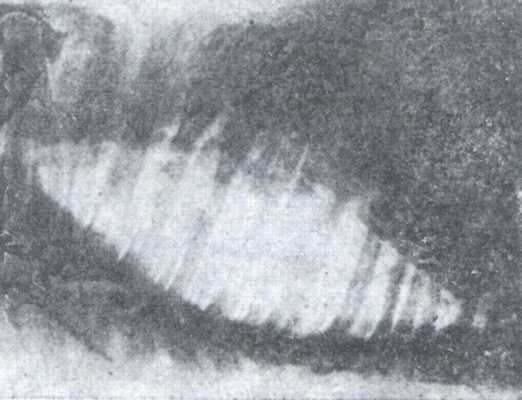

Рентгенодиагностика бронхопневмонии: Советы и примеры

Раздел: Альбом открытий